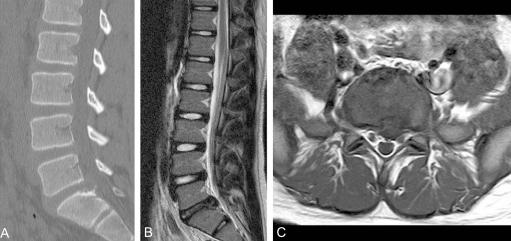

To assess the radiological, clinical features and surgical outcomes of six patients of elementary school age with lumbar disc herniation (LDH).

The surgical findings revealed a protruding disc in five cases and a ruptured disc in one. In addition, separation of the vertebral ring apophysis was observed in 3 cases. The symptoms had disappeared completely at the last follow-up. At the last follow-up, the Japanese Orthopaedic Association score was 10 points in 5 cases and 9 points in 1, and the Kirkaldy-Willis criteria was excellent in all patients. No intervertebral disc space narrowing was observed in any patient at last follow up. In addition, there were no degenerative changes in the vertebral endplate and facet joint.

评估6例小学年龄腰椎间盘突出症(LDH)患者的影像学、临床特征及手术疗效。

手术发现5例为椎间盘突出,1例为椎间盘破裂。此外,3例观察到椎环骨骺分离。末次随访时症状已完全消失。末次随访时,日本骨科协会评分为5例10分,1例9分,所有患者的Kirkaldy-Willis标准均为优。末次随访时所有患者均未观察到椎间盘间隙变窄。此外,椎体终板和小关节无退变改变。